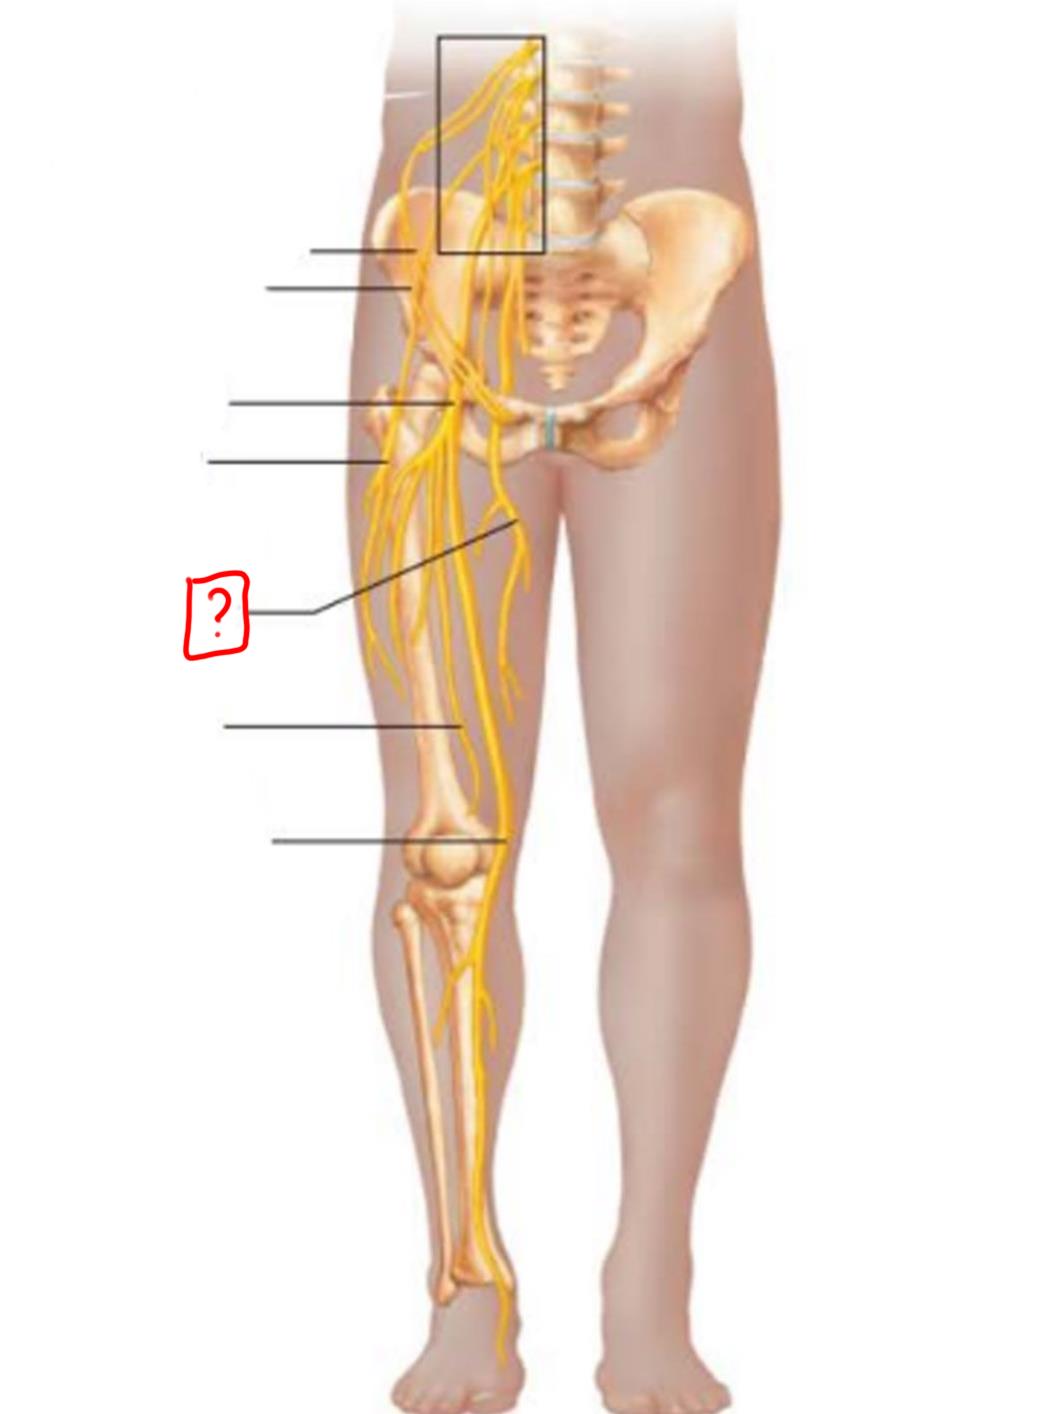

iliohypogastric

ilioinguinal

genitofemoral

lateral femoral cutaneous

obturator

femoral

lumbosacral trunk

iliohypogastric

ilioinguinal

femoral

lateral femoral cutaneous

obturator

anterior femoral cutaneous

saphenous